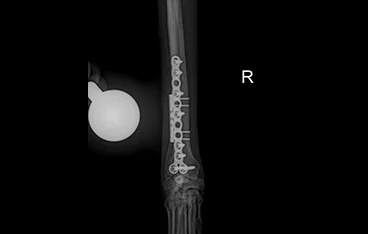

• PLATE

• PLATE 수술 전

PLATE 수술 후